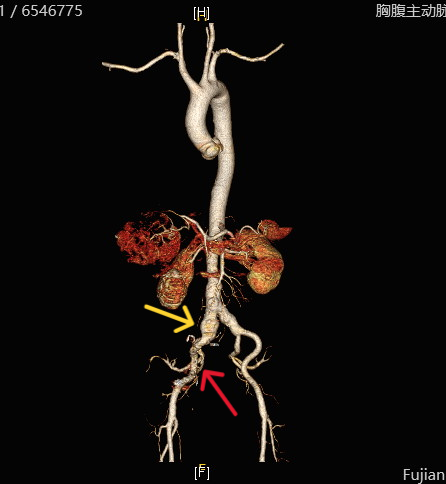

祸不单行,陈老师的术前检查还提示胰腺体部存在 2.5×1.5cm的占位。得益于我院先进的磁共振和PET-CT 检查,精准为外科手术提供了重要依据。这处占位可疑来源于肝癌的转移病灶,肝癌转移到胰腺的情况在临床上非常罕见,文献报道仅占2.7-5.6%。

图示胰腺转移灶